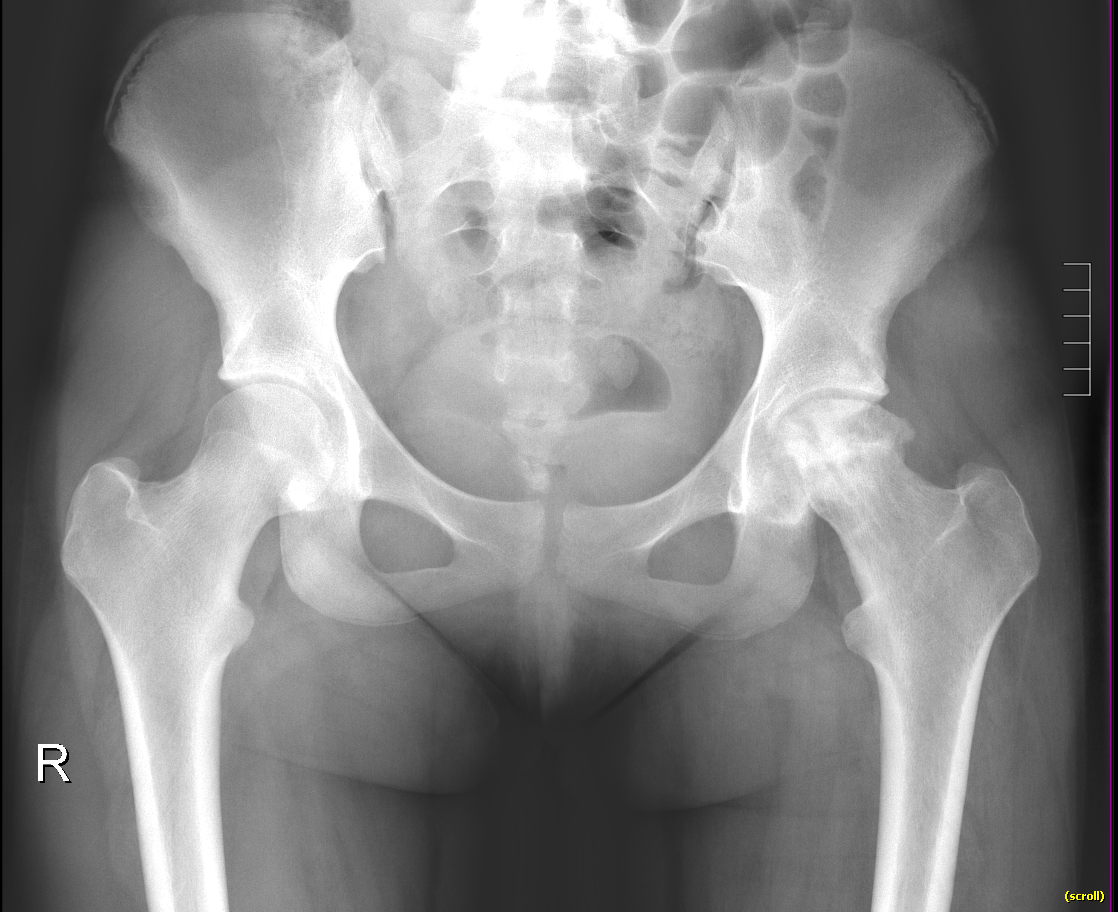

Info Images Findings Impression Reco/Acuity Case Images View Images / Launch Visage Case Notes History 2-month-old presents with decreased right arm movement, increased fussiness, and increased sleepiness for 2 days. Suspected non-accidental trauma. Exam Skeletal survey Prior Study none Dicom View Reference Material

Section 1 Submit Findings CB1550 Findings Skeletal Survey - Technique Check Skull AP/Lat Yes No Cervical and Thoracolumbar spine Yes No Chest X-Ray Yes No Ribs – Left/Right Oblique Yes No Abdominal X-Ray Yes No Pelvis with both hips Yes No Bilateral Humerus, Forearm, Hand Yes No Bilateral Femur, Tibia/fibula, feet Yes No Any additional lateral views of the extremities Yes No The exam is over or under penetrated. Yes No The exam may or may not be limited by overlying structures or soft tissues, body habitus, patient positioning, support devices, or motion. Yes No The area of concern is indicated by the patient, technologist, or care provider. Yes No The area of concern is included on the exam. Yes No Soft Tissues There is soft tissue swelling, indistinctness of fat/muscle planes, gas, or laceration in the area of clinical concern. Yes No There is an effusion, fat pad displacement, or fat fluid level. Yes No There is a radiodense or lucent foreign body. Yes No There are other densities, calcifications, post-surgical changes, or support devices in the soft tissues. Yes No Any support lines/tubes. Yes No Bone There is a break or interruption of the continuity of the cortical or cancellous bone. Yes No There is overriding of the trabeculae with apparent sclerosis. Yes No There is displacement of a fracture fragment. Yes No There is bowing of the bone in addition to the fracture at the apex of the bowed bone concerning for the greenstick. Yes No There is a spiral fracture of the leg concerning for toddler’s fracture. Yes No There is abnormal angulation or bulging of the cortical surface relative to the normal cortex which could be from a buckle or torus fracture. Yes No There is a displaced fragment which may be from avulsion by a tendon, ligament, or joint capsule or from a comminuted or other fracture. Yes No The stress trabeculae or other trabeculae of the cancellous bone are interrupted or otherwise abnormal. Yes No There is subperiosteal or endosteal reaction which could indicate a healing or subacute fracture or other abnormality. Yes No There is hard/soft callus formation. Yes No There is remodeling of the bone. Yes No There is a corner fracture or metaphyseal lesion that could be from nonaccidental trauma. Yes No There are multiple fractures of different ages. Yes No There are vertebral body/spinous process fractures. Yes No There are rib fractures. Location - posterior or lateral. Yes No There is scapular/sternal fracture. Yes No There are fractures of the digits. Yes No There are wormian bones. Yes No There are intrasutural bones. Yes No There is metaphyseal abnormality (lucencies, increased density, erosion) which may be from something other than injury such as stress, metabolic disease (e.g. rickets with loss or distortion of the zone of the provisional calcification), neoplasm (e.g. leukemia), heavy metals, inflammation, or infection. Yes No There are metaphyseal spurs. Yes No There are bony deformities involving multiple bones. Yes No The bones are gracile. Yes No There are non-healing fractures. Yes No There is/are focal or multifocal lytic/lucent, blastic/sclerotic or mixed density lesion(s) or other abnormality. Yes No Overall bone density is increased or decreased with or without thinning or thickening of the cortical or cancellous bone. Yes No Growth plates, ossification centers, apophyses The growth plate(s) is/are abnormal. Yes No There is widening of the physis from a fracture with or without displacement of the epiphysis (Salter-Harris I). Yes No There is a fracture through the physis which then extends into the metaphysis with or without angulation or displacement (S-H II). Yes No There is a fracture through the physis which then extends into the epiphysis and is intra-articular, with or without angulation or displacement (S-H III). Yes No There is a fracture through the metaphysis, physis, and epiphysis which extends into the joint space with or without angulation or displacement (S-H IV). Yes No There is narrowing of the physis from a compression fracture (S-H V). Yes No The apophysis, epicondyle, secondary ossification center, or accessory ossicle is displaced or otherwise abnormal. Yes No The ossification centers are underdeveloped. Yes No Joints and alignment There is an effusion, fat pad displacement, or fat fluid level. Yes No The epiphysis or subchondral bone is fractured, interrupted, flattened, compressed, impacted, displaced, or otherwise abnormal. Yes No There is an intra-articular loose body or chondrocalcinosis. Yes No The joint is widened, narrowed, dislocated, malaligned, or incongruent. Yes No There is pseudoarthrosis. Yes No Other findings There are developmental changes or other anatomic variants or other existing conditions that may or may not be contributing to symptoms which can or should be further evaluated non-emergently or are otherwise incidental. Yes No The remainder of the exam is abnormal for age. Yes No The lungs show focal airspace opacity. Yes No There is pneumothorax. Yes No There is organomegaly. Yes No There is intra-abdominal calcification. Yes No There is displacement of the bowel loops. Yes No There is free intraperitoneal air. Yes No The bowel loops are dilated/obstructed. Yes No There is paraspinal soft tissue abnormality. Yes No